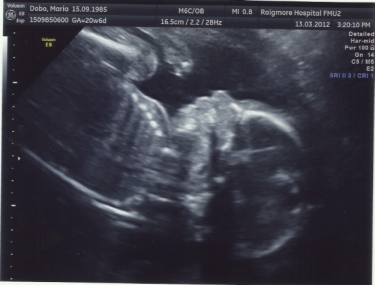

Niki: félidőőőőőő!!!